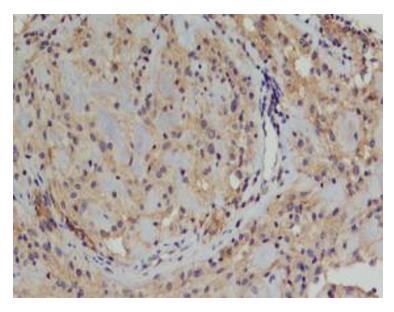

图6 瘤体细胞细胞质嗜酸性,淡染,核分裂不易见,瘤细胞间见均匀红染的基底膜样物(HE,×200)

Figure 6 The tumor cell cytoplasm is eosinophilic, pale, nuclear division is not readily visible, and uniform samples of red-stained basal membrane are visible between the tumor cells (HE, ×200)

20230106100605_4778.jpg

biomicroscopy,UBM)显示虹膜根部向前膨隆与角巩膜缘相贴,局部方向虹膜后见中等回声隆起(图3 )。临床诊断:左眼虹膜睫状体肿物,左眼并发性白内障。于2021年12月23日行“虹膜睫状体肿物切除术,左眼白内障超声乳化抽吸术”,术中左眼6点位睫状体部可见大小约3 mm灰黄圆形隆起,表面光滑,部分与晶状体轻微粘连,易剥离。手术中切除的肿瘤组织(图4)行常规病理检查:苏木精-伊红(hematoxylin-eosin,HE)染色可见肿瘤低倍镜为边界清楚的结节状,细胞呈腺腔样排列,部分为条索状,瘤细胞细胞质嗜酸性,淡染,未见色素颗粒(图5);部分间质黏液样变性,瘤细胞间见均匀红染的基底膜样物(图6)。高倍镜下瘤细胞胞核呈圆形或卵圆形,染色质分布均匀,偶可见小核仁,未见核分裂。过碘酸雪夫(periodic acid-SchiffPAS)染色瘤细胞间基底膜样物为阳性( 图 7 ) 。免疫表型:肿瘤细胞表达 S-100 、Vimentin、CK8/18、EMA、CKpan、Melan-A,Ki-67标记指数为5%,而GFAP、CEA、P63、HMB-45均为阴性(图8~10)。病理诊断:左眼ANPCE。手术后查体:右眼远视力1.0,左眼远视力0.06;右眼矫正视力:+0.5ODS→1.0,左眼矫正视力:矫正无助;右眼眼压:13 mmHg,左眼眼压:6 mmHg;术眼结膜充血水肿(++),角膜后弾力层褶皱明显减轻,前房深度可,瞳孔竖椭圆形,直接对光反射消失,晶体缺如。截至随访日期,术后3个月无疾病进展。